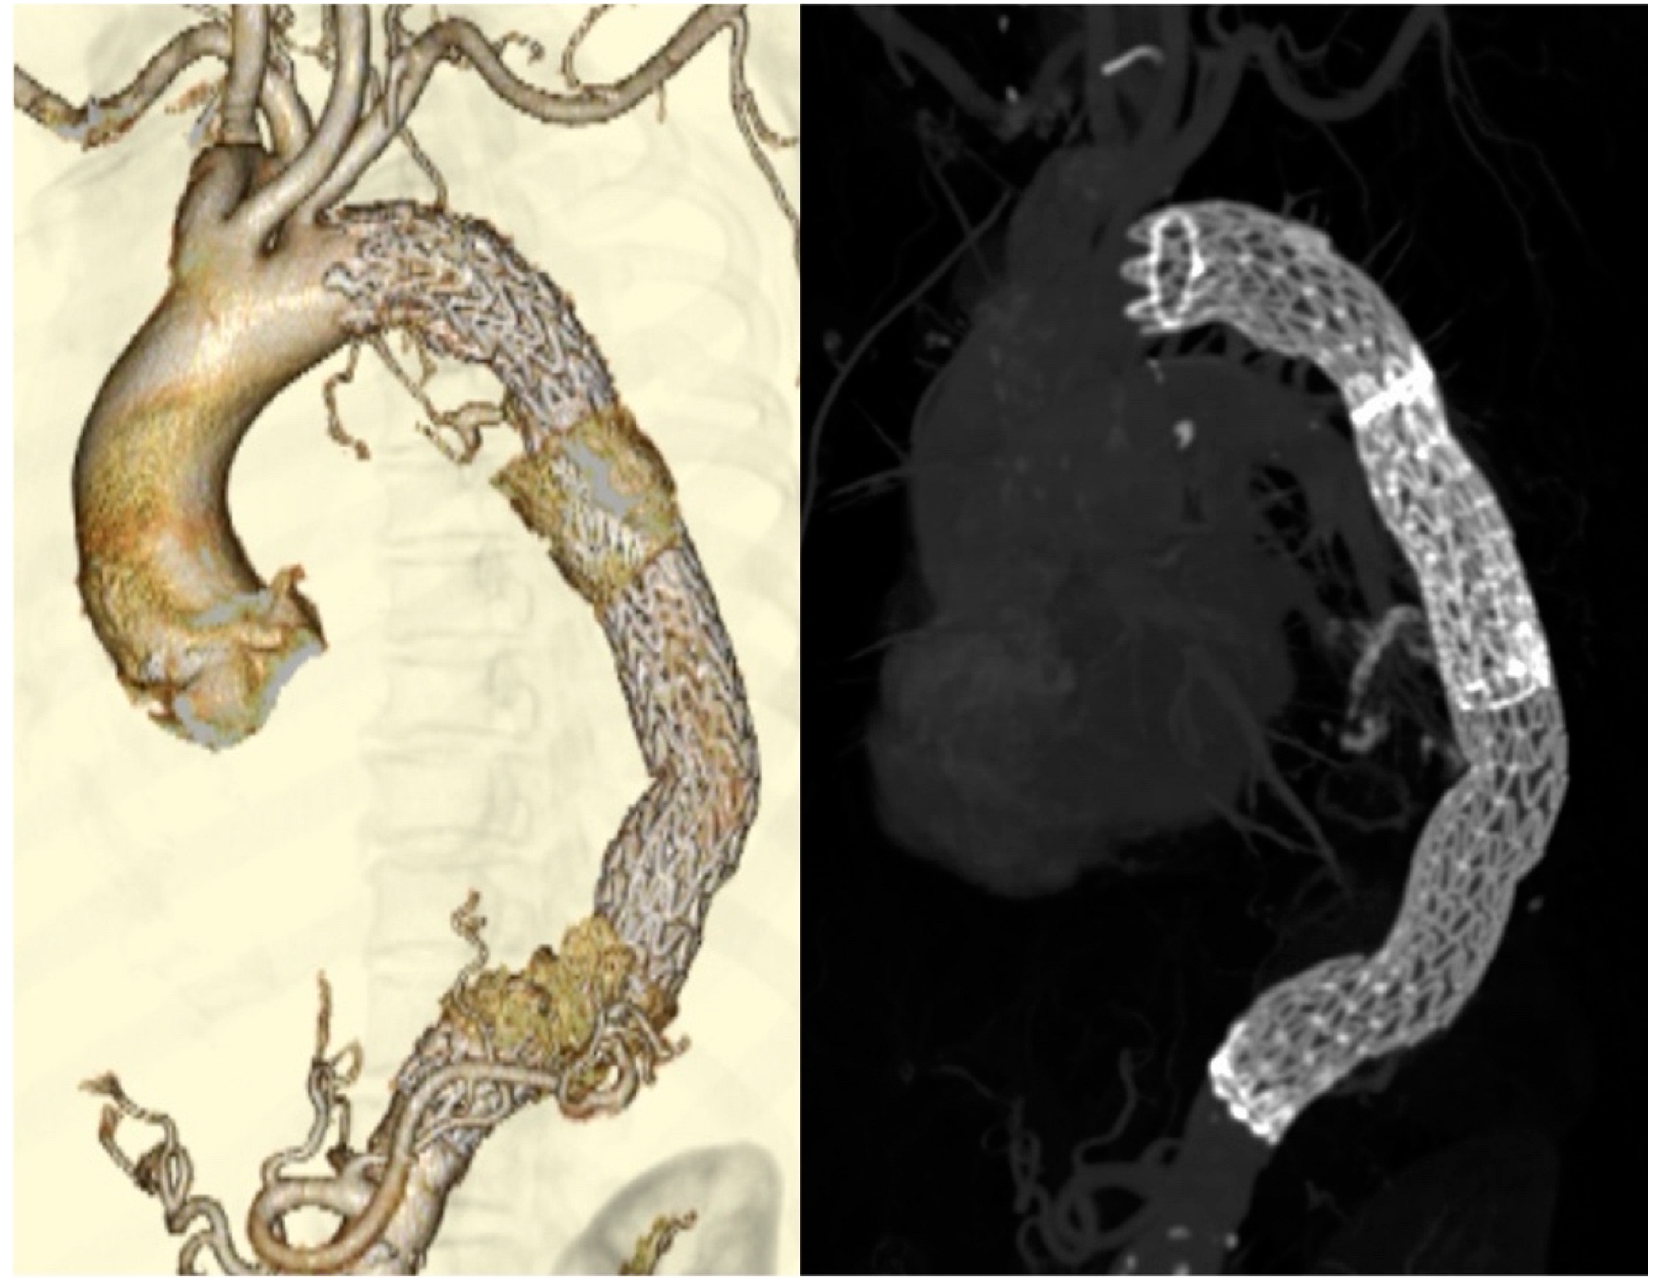

A 77-year-old woman underwent graft replacement of the descending aorta for a descending aortic aneurysm 18 years prior. Postoperatively, aortic dissection was observed at the proximal and distal anastomoses of the graft, and the patient was regularly followed up with computed tomography (CT) in the outpatient department. At 3 months prior to admission, the patient developed a cough with bloody sputum, and due to the persistent symptoms, she was admitted for a thorough examination. On admission, a contrast-enhanced CT scan showed infiltrative shadows and gaseous images in the lung fields around the graft (Figure 1). Gallium scintigraphy also showed abnormal accumulation of gallium consistent with the infiltration shadows and gas images of the lung fields observed on contrast-enhanced CT (Figure 2). Based on these imaging findings, ABF was diagnosed. The patient was considered to be at high risk owing to her advanced age and post-graft replacement of the descending aorta; therefore, TEVAR was performed on the 11th day after admission.

Figure 2. Gallium scintigraphy showing abnormal accumulation of gallium (red circle), consistent with the infiltrating shadow and gas image of the lung fields seen on contrast CT. CT, computed tomography.